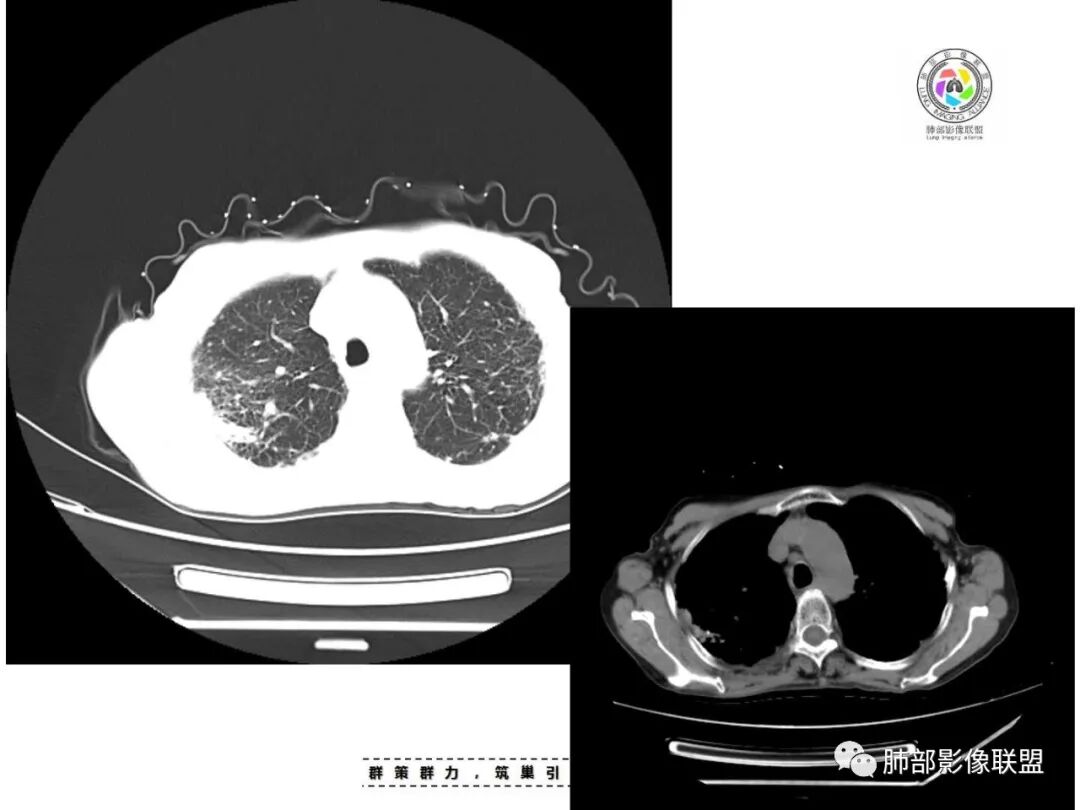

老年女性,67岁,咳嗽、咳痰半月余。双肺可闻及痰鸣音。

胸部CT:双肺上叶多发小结节,沿胸膜下、支气管血管束分布。右上肺斑片实变影、索条影及小叶间隔不均匀增厚,支气管枯枝征?纵隔淋巴结多发肿大,部分有钙化。综合考虑:结节病?尘肺?鉴别:腺癌并癌淋。

患者老年女性,亚急性起病,主要症状表现为咳嗽、咳痰半月余,查体:双现呼吸音粗,双肺可闻及痰鸣音。胸部CT:双上肺胸膜下可见多发小叶实变影,双上肺可见多发小叶中心性结节及小叶间隔增厚,右上肺后段可见亚段性实变影,内见多发空洞,前段可见GGO及树芽征,后段局部支气管闭塞,肺门淋巴结肿大并钙化。病灶整体:有气道、间质播散,一元论考虑肺结核合并支气管结核可能性大,建议好好查痰;这样病灶:明显实变+空洞+气道播散,若是结核,痰涂片找到抗酸杆菌应该没问题。建议支气管镜检查助诊,了解有无支气管结核及合并腺癌的可能。

1.双肺片状影、大小不等斑片影、结节影、树芽等,病灶密度偏高多钙化。

2.病灶上肺为主,胸膜下分布为主。双肺病灶明显不对称,右肺块状影较大。

3.纤维条索影广泛杂乱、牵拉,横向分布为主,这点给人也印象很深!

4.纵隔轻度右移。双肺门纵隔淋巴结增大钙化。

5.老年女性患者,咳嗽咳痰半月余